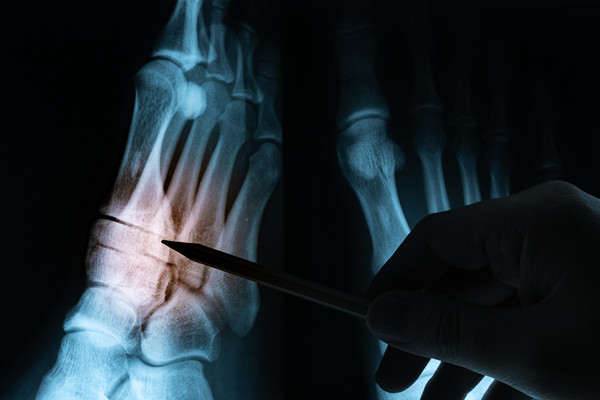

主要适合骨与关节结核中后期、寒性脓肿形成或伴有窦道死骨形成、全身截瘫者。其手术目的是消除脓肿、干酪组织、死骨,切除久治不愈的窦道。不过手术前后仍然需要进行全身抗痨治疗。